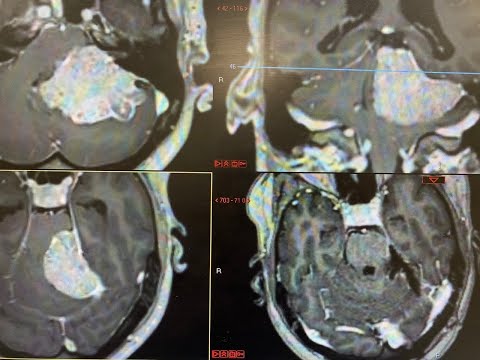

Hellow guys, Welcome to my website, and you are watching Cerebellopontine Angle Meningioma- מנינגיומה של גזע המוח-דר׳ משה עטיה. and this vIdeo is uploaded by Dr. Moshe Attia (דר' משה עטיה) at 2022-01-01T23:36:57-08:00. We are pramote this video only for entertainment and educational perpose only. So, I hop you like our website.